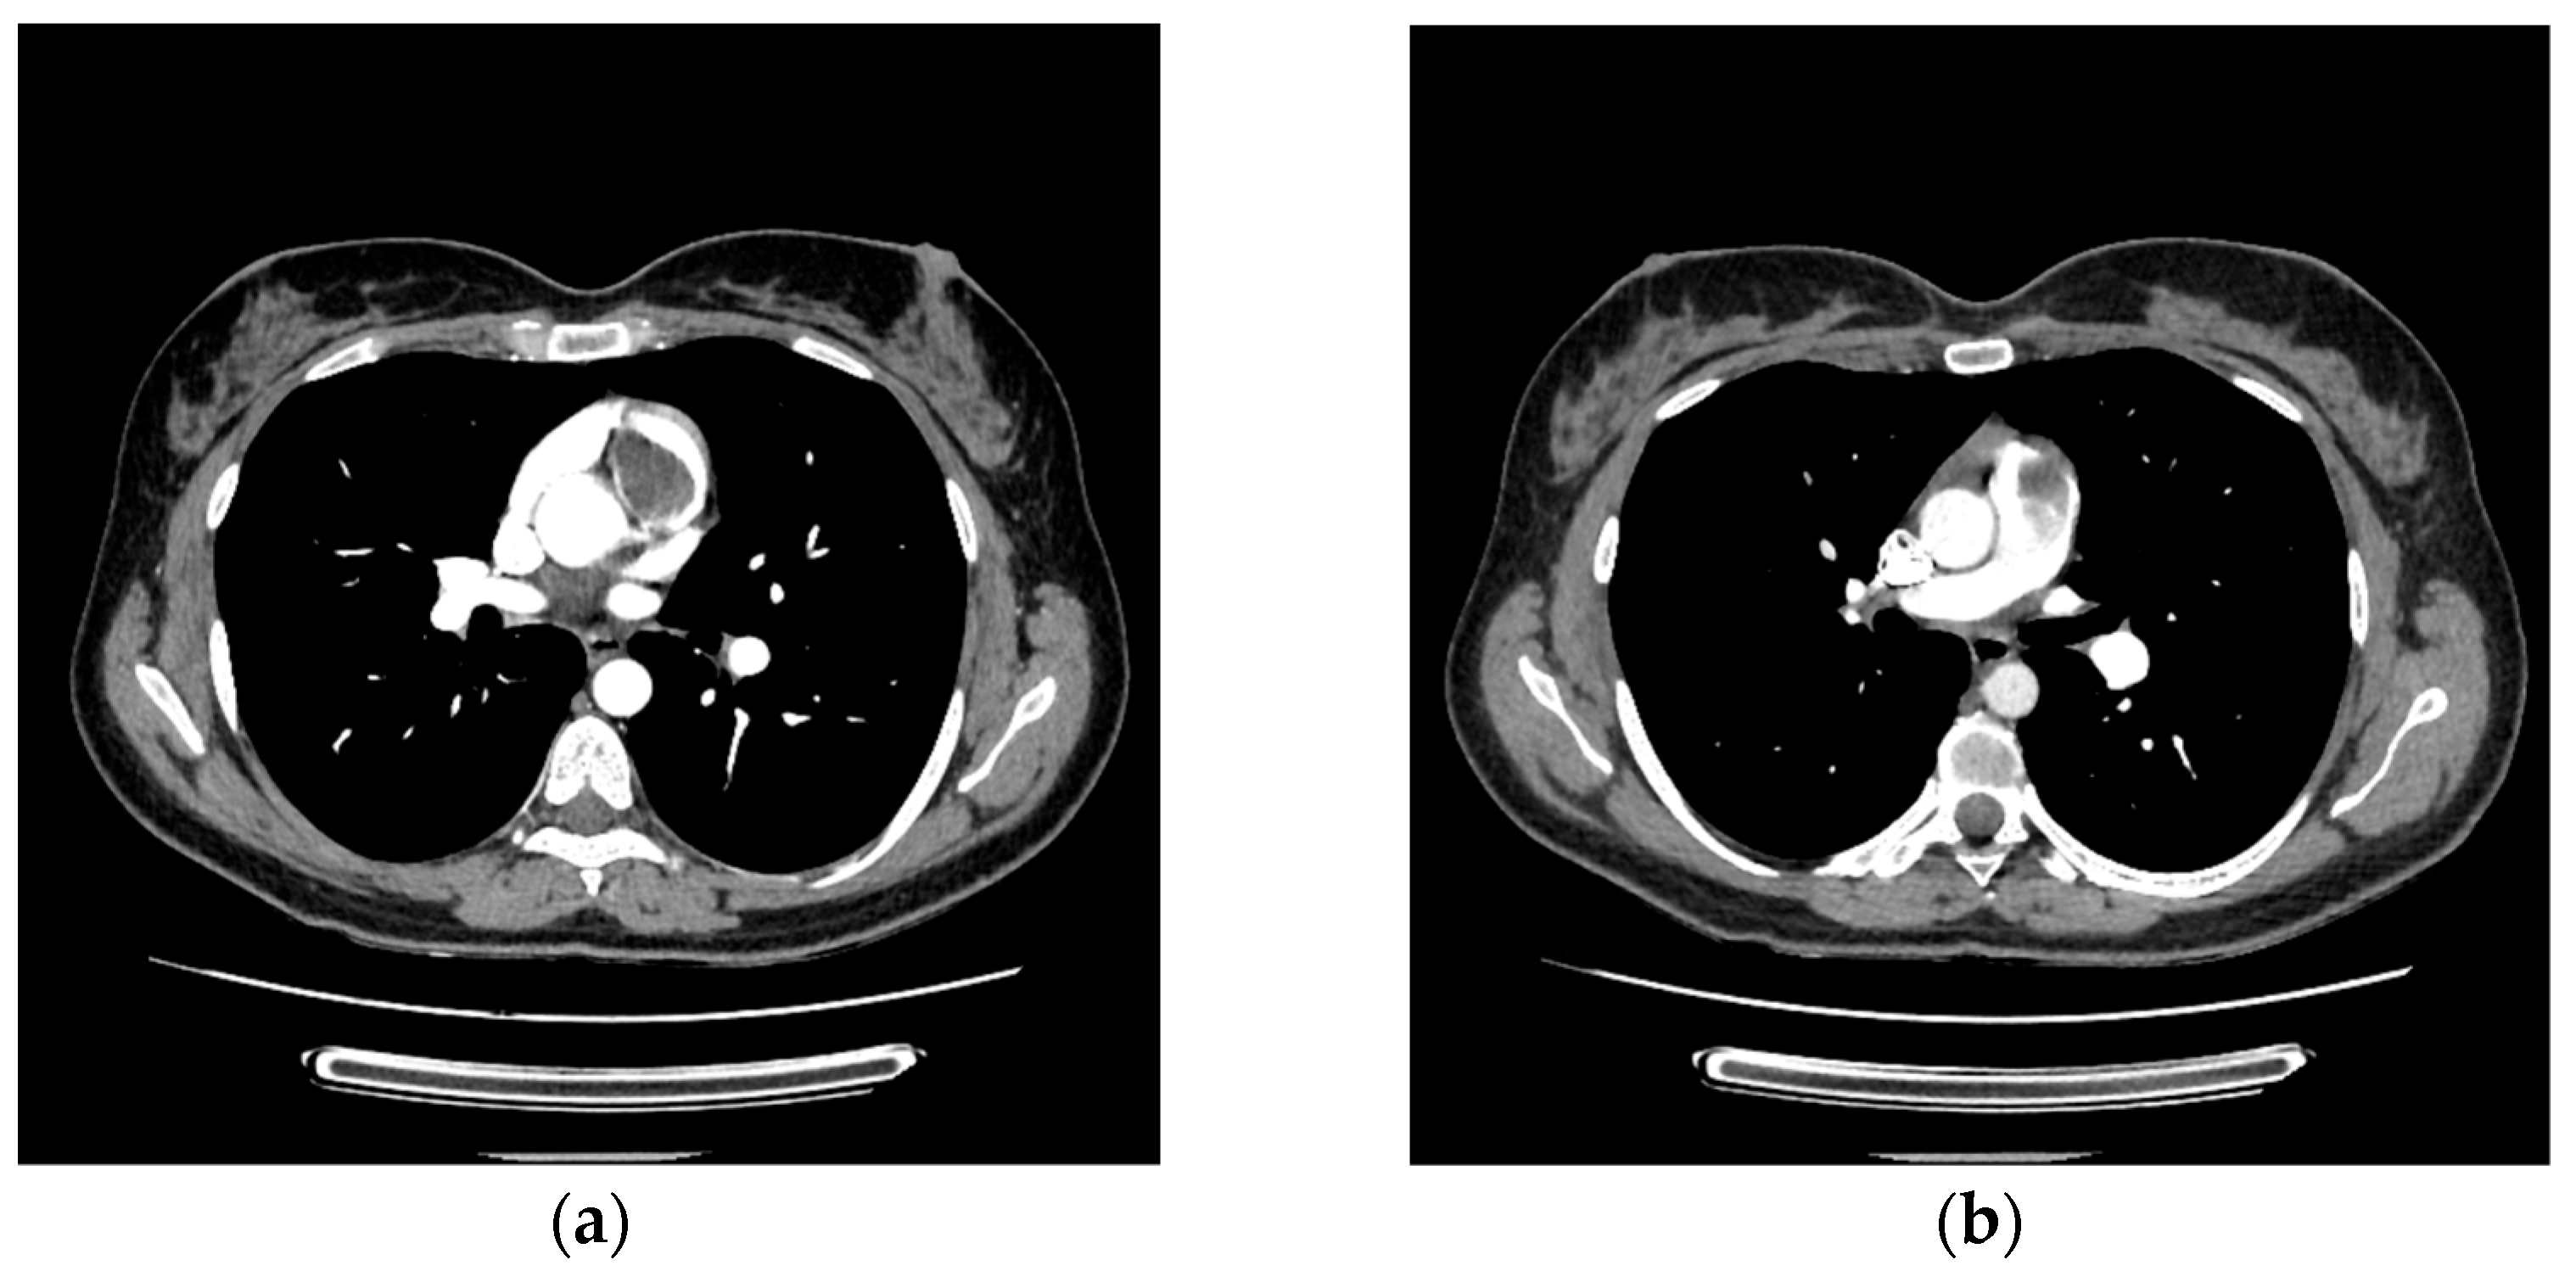

2. Case Report